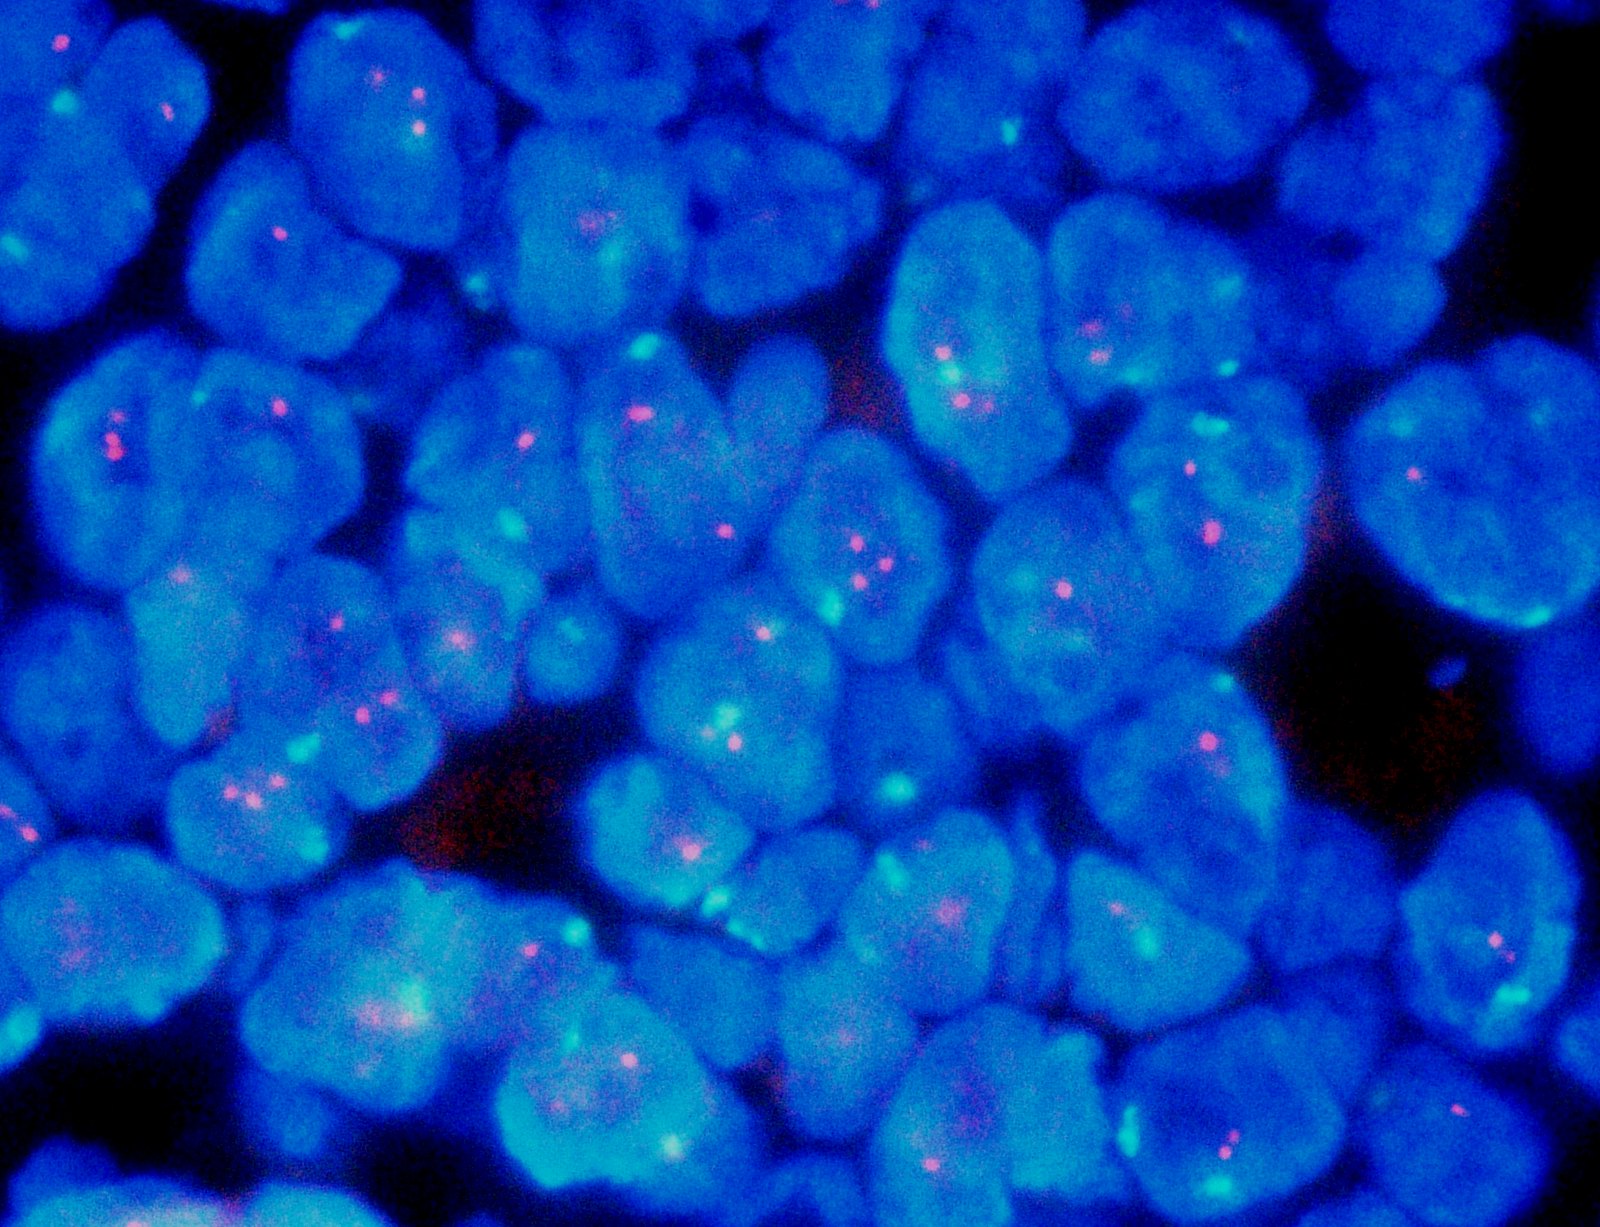

Molecular / cytogenetics images